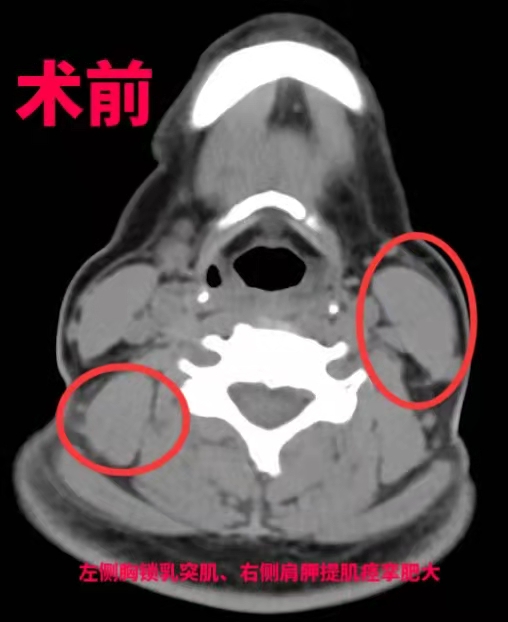

主任王向宇教授告诉南都记者,困扰钟女士6年的“怪病”真正的诊断是痉挛性斜颈,属于肌张力障碍,人们俗称“歪脖子”病,主要是由于颈部肌肉痉挛,导致头颈部无法摆正,偏向前后左右任何的一边。

导致痉挛性斜颈作用的原理是比较清晰的,大就是被部分神经控制的肌肉群过于亢奋和紧张。在不能损毁肌肉导致大面积创伤的情况下,通过神经外科手术离断关键的支配神经的神经根,就能缓解肌肉群的过度亢奋。

“最好的方式是手术,考虑到钟女士年轻还要负担一家老小,我们决定选择用‘超选择性神经根切断术’治疗她的痉挛性斜颈。”王向宇表示,相比于其他方式,这种术式需要在术前进行详细检查和评估,通过影像、肌电图检查、选择性肌肉阻滞等专业方法,事先找到“肇事”肌肉,在术中用最小电量反复刺激,精准找到这些“肇事”肌肉的支配神经,进行选择性的神经根切断,而不伤害其他神经和肌肉,进一步减少损伤。经过6个小时后,手术宣布成功,钟女士经过1周的恢复,“歪脖子”的问题得到了根本性解决。